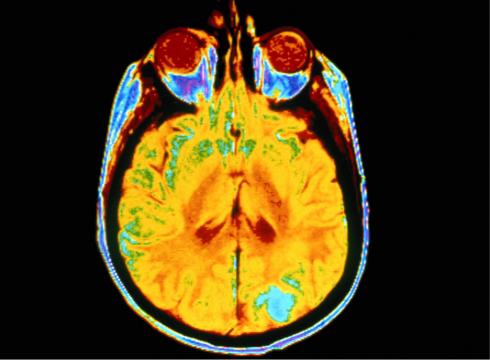

Most strokes are caused by a blood clot that blocks the flow of blood to the brain, depriving it of oxygen. Desmoteplase helps dissolve the clot thereby opening the blood vessel to restore blood flow. The local hub of this international trial is The Massachusetts General Hospital in Boston.